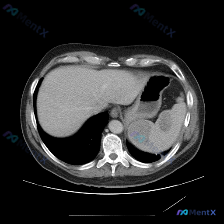

这是一张上腹部横断面CT平扫(软组织窗):

- 肝脏:形态大小、实质密度都还好,没看到明确占位,肝门血管也清晰;

- 脾脏:是最显眼的地方——多个类圆形低密度灶,边缘比较清晰,密度比正常脾实质明显低;

- 其他:胃、腹主动脉、膈肌、胸腔下部都没看到明显异常。